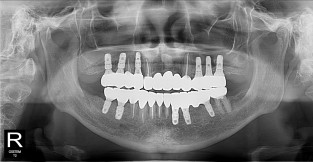

• 9

무치악

치료기간 : 2023-02-21 ~ 2023-10-21

1. 상기 x-ray 이미지 모두 동일한 해당 의료기관에서 진료한 환자입니다.

2. 상기 x-ray 이미지 모두 동일 인물의 것입니다.

3. 치료 전 이미지는 2023-02-21에 촬영했으며, 치료 후 이미지는 2023-10-21에 촬영하였습니다.

4. 상기 x-ray 이미지 모두 동일 조건에서 환자분의 동의를 받아촬영되었습니다.

* 임플란트 시술은 환자분의 상태(고혈압, 당뇨 등)에 따라 부작용이 있을 수 있으니, 반드시 전문의와 상담이 필요합니다.

* 임플란트 수술 부작용

: 수술 후 출혈, 교합, 통증, 붓기, 염증 등의 문제점이 발생할 수 있습니다.)